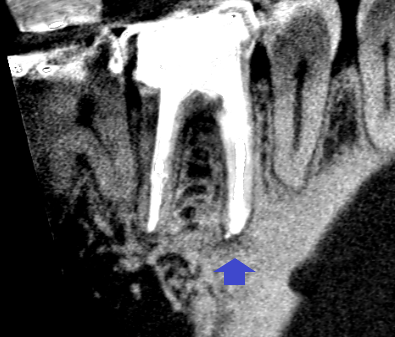

精密根管治療6カ月後の経過観察時の矢状断のCT画像です。下顎第一大臼歯の矢印の先にあった膿の影が消え、歯槽骨が再生しています。

精密根管治療6カ月後の経過観察時の冠状断のCT画像です。根の先にあった膿の影が消え、歯槽骨が再生しています。イスムスも清掃・根管充填されています。